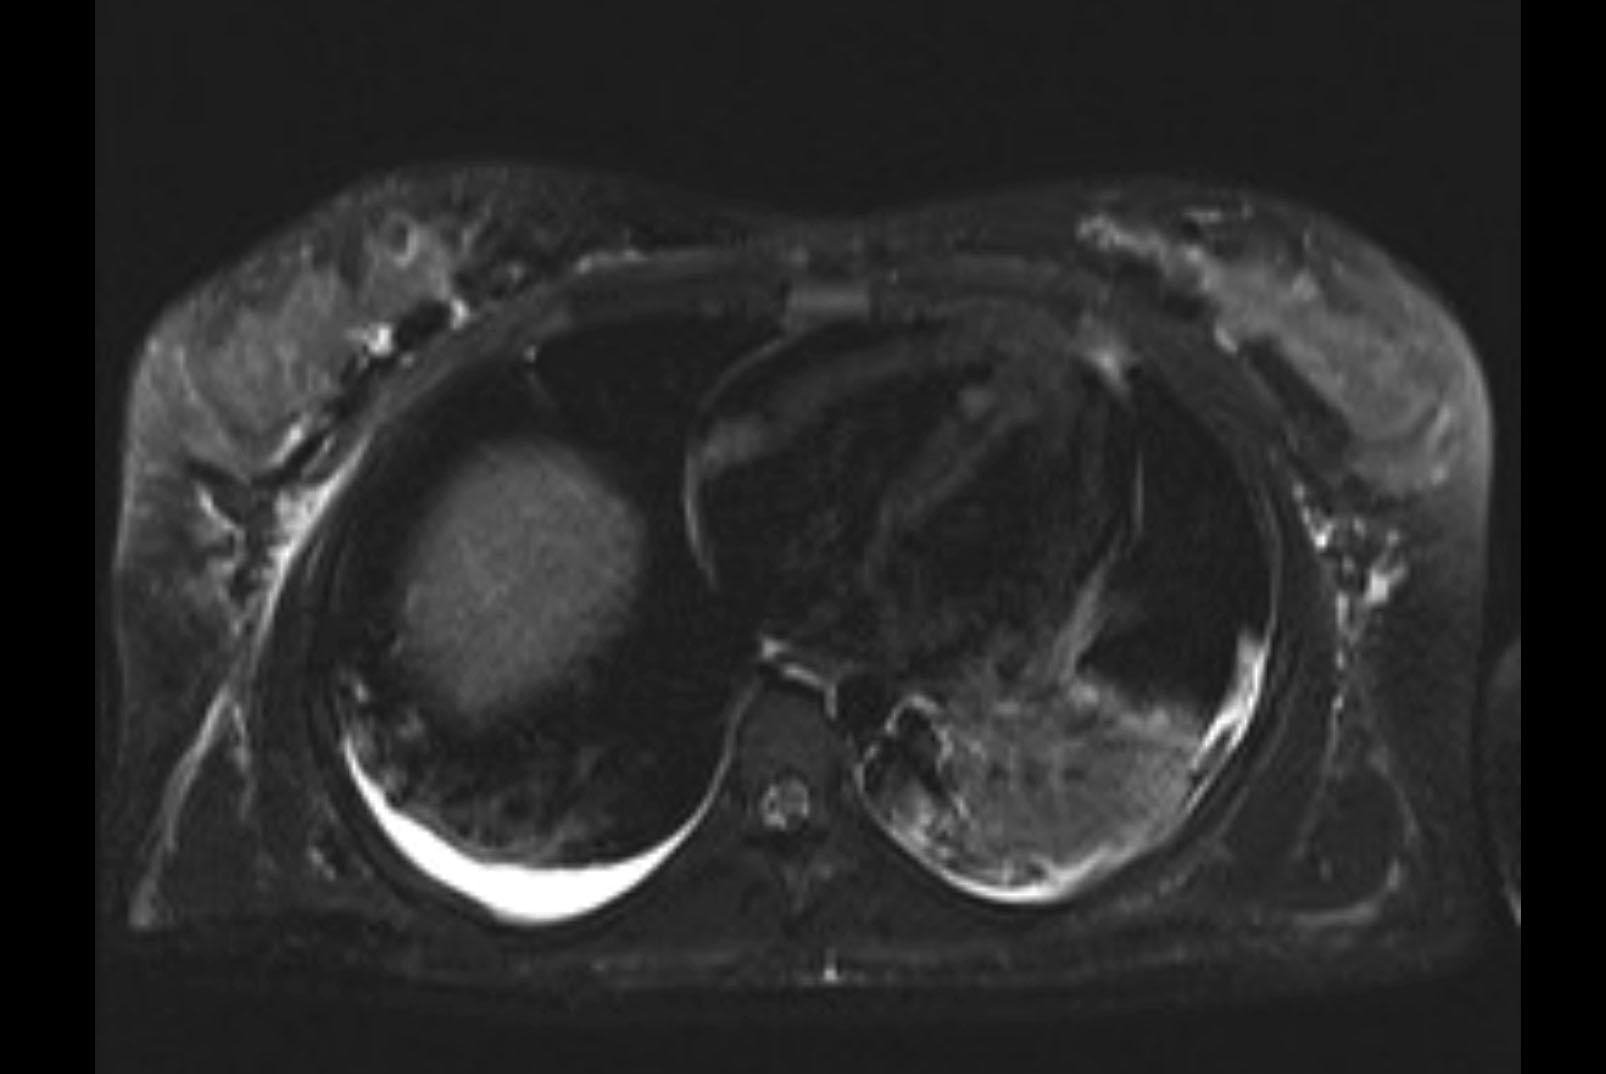

MRI T2

Imaging analysis

Based on initial findings, which issue(s) would you be most concerned about?